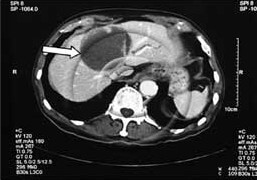

Figure 1. Yttrium 90 microspheres

Radioactive material gives off invisible rays which can cause harm and death to normal or cancerous cells. The most obvious example of radiation treatment used to treat cancer is in breast cancer. The rays are delivered from a machine onto the breast or the chest wall in an attempt to reduce the risk of recurrent breast cancer. In SIR therapy, the appropriate amount of radiation material, called yttrium-90 (y-90), is delivered in the form of microscopic spheres into the liver cancer via the hepatic artery. These radioactive microspheres (Figure 1), once deposited into the cancerous tumour, will emit the invisible rays and kill the cancer cells.